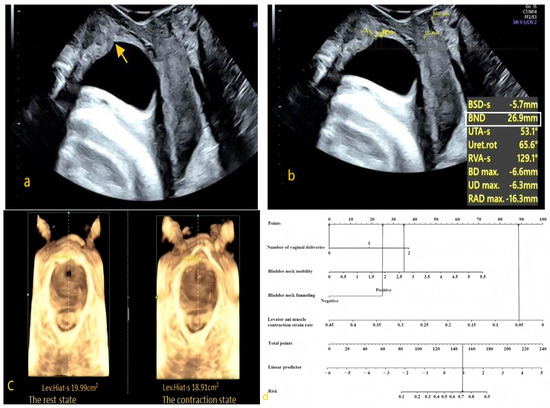

- Examination Method: After the patient emptied their bladder and bowels, they were positioned supine on the examination table with their legs flexed and mildly abducted in the lithotomy position. The specialized probe was wrapped and a large amount of disinfectant gel was applied to avoid air interference within the probe cover, ensuring good image quality. The probe was placed between the labia, and images of the pelvic floor in the mid-sagittal plane were obtained in three conditions—at rest, during maximal voluntary contraction, and during a Valsalva maneuver. The structures examined included the pubic symphysis, urethra, bladder, vagina, rectum, anal canal, and anorectal angle. Using the pubic symphysis as the central reference point, the sagittal plane images of the vagina, urethra, and anal canal were captured. Volume scanning was then performed, with appropriate adjustment of the selected region to collect two-dimensional and four-dimensional ultrasonographic images of the pelvic floor at rest, during maximal voluntary contraction, and during the Valsalva maneuver (Figure 2).

- Observation Indicators: (1) bladder neck vertical position, which is the vertical distance from the bladder neck to horizontal level of the posterior-inferior margin of the pubic symphysis; (2) bladder neck descent, which is the difference in the bladder neck position between the maximum Valsalva and resting states; (3) bladder–urethra posterior angle, which is the angle between the posterior wall of the bladder (trigonal region) and proximal urethra; (4) urethral rotation angle, which is the difference in the urethral inclination angle between the maximum Valsalva maneuver and resting states; (5) bladder neck funneling; (6) hiatal area (HA),the area enclosed by the pubic rami, pubic symphysis, and the medial border of the puborectal muscle; and (7) the levator ani muscle contraction strain rate, which is the difference in the hiatal area (HA) between the resting and contraction states, divided by the HA in the resting state.